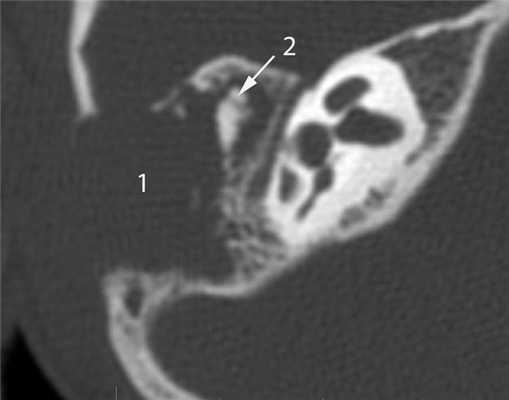

КТ-признаки злокачественной опухоли височной кости предопределяются происходящими в ней патоморфологическими изменениями. Так, наличие опухолевых масс в среднем ухе на КТ проявляется нарушением пневматизации полостей среднего уха (рис. 1). Рисунок 1. Лангергансоклеточный гистиоцитоз. Аксиальная проекция правой височной кости. Отсутствует пневматизация полостей среднего уха за счет наличия опухоли (1), вызывающей обширные деструктивные изменения в пирамиде. Цепь слуховых косточек сохранена (2). Степень выраженности данного КТ-симптома обусловлена размерами самой опухоли и ее точной локализацией в височной кости. Нарушение пневматизации полостей среднего уха не является специфичным для новообразований и постоянно встречается при других заболеваниях среднего уха, в первую очередь при остром и хроническом средних отитах.

Частым проявлением опухоли височной кости, как было сказано выше, является ее распространение в наружный слуховой проход, что находит свое отражение и на КТ. При небольших размерах полипозного новообразования на КТ в просвете наружного слухового прохода визуализируется образование, исходящее из барабанной полости или проникающее в слуховой проход через его разрушенную стенку (рис. 2). Рисунок 2. Лангергансоклеточный гистиоцитоз. Коронарная проекция правой височной кости. В наружном слуховом проходе определяется полипозное образование (1), на уровне которого верхняя стенка НСП деструктивно изменена. Нарушена пневматизация среднего уха (2). Большой «полип» проявляется на КТ полной обтурацией воздушного просвета слухового прохода мягкотканным образованием (рис. 3). Рисунок 3. Рабдомиосаркома. Аксиальная проекция левой височной кости. Отсутствует пневматизация костного устья слуховой трубы и барабанной полости (1). Просвет наружного слухового прохода обтурирован мягкотканным полипозным образованием (2). Деструкция задней стенки барабанной полости и наружного слухового прохода (3). При анализе данного КТ-признака следует учитывать, что истинные полипы, встречающиеся при хроническом гнойном среднем отите, в отличие от опухолей имеют излюбленную локализацию и чаще всего исходят из верхних отделов барабанной полости.